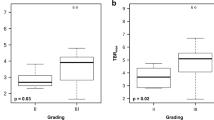

FET PET for differentiation of tumour progression from treatment-related changes

In patients in whom the diagnosis confirmed tumour progression (nine patients), all corresponding FET PET scans showed increased uptake (TBRmax 3.5 ± 0.6, range 2.5–4.4; TBRmean 2.7 ± 0.7, range 2.0–4.0). In four of these nine patients, tumour progression was diagnosed histologically. Imaging and histology in a representative patient (patient 11) are presented in Fig. 1. In patients in whom the diagnosis of tumour progression was confirmed clinically (five of nine patients), the median follow-up was 4 months (range 3–6 months). Static data on FET uptake in the lesions are presented in Table 1. Furthermore, in three of these nine patients, a baseline FET PET scan prior to initiation of neurooncological treatment including TTFields was available (patients 3, 4 and 6; Table 1). Compared with baseline, either a significant increase in the metabolically active tumour volume (patient 4; Fig. 2) or a significant increase in TBR (patients 3 and 6) on FET PET were observed. In patient 3, TBRmax increased from 3.2 to 3.9 (22%) and TBRmean from 1.9 to 2.3 (21%). In patient 4, TBRmax increased from 1.9 to 2.8 (47%), and TBRmean from 1.7 to 1.9 (12%). In patient 4, the metabolically active tumour volume increased significantly from 9 ml (at baseline) to 42 ml (at 9 months; Fig. 2).